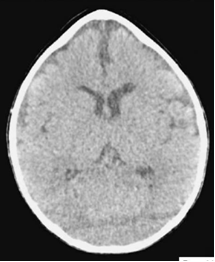

д) Диагностика. Рентгенологические признаки краниосиностозов (Avivet al., 2004) включают заметное усиление пальцевых вдавлений, особенно выраженных при сращении нескольких швов (рис. 5.5). При сагиттальном краниосиностозе обычно отмечается двустороннее преобладание пальцевых вдавлений в области лба. Бороздки от венозных синусов глубокие и хорошо видны. Возможное выраженное увеличение и эрозии спинки турецкого седла. Описанные признаки, которые в некоторых случаях могут выявляться при бессимптомном течении заболевания, свидетельствуют о длительном повышении ВЧД, подтверждаемым непосредственным измерением. Швы не видны, а в области их нормального расположения отмечается гиперостоз.

Тем не менее, на ранней стадии линия шва может быть видна частично или полностью. В таких случаях диагноз устанавливается на основании узкой и прямой линии шва и уплотнения краев шва.

Микроцефалический синостоз (рентгенограмма). Все швы сращены.

Кости свода черепа тонкие с заметными пальцевыми вдавлениями. Венозные синусы глубоко проникают в кость (7-летний мальчик с внутричерепной гипертензией и отеком диска зрительного нерва.

Заболевание одновременно отмечалось у двух сибсов. В обоих случаях умственное развитие не отличалось от нормы).

Рис. №2 а) – вариант нормы

б) – деформация черепа вызванная синостозом (слиянием) лямбдовидного шва слева, указателем показаны множественные пальцевые вдавления (истончение костной ткани, вплоть до появление «дыр»).